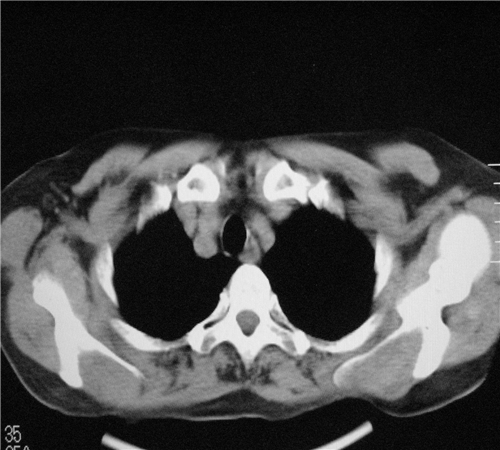

标题: CT26849:女67岁反复胸痛两天余,临床考虑夹层。 [打印本页]

标题: CT26849:女67岁反复胸痛两天余,临床考虑夹层。

右肺感染,未见夹层。

升主动脉增宽是怎么回事啊!食管有事吗?老师

既然考虑夹层,建议强化!另:右下肺感染!

1)右肺感染性病变。2)建议行ct增强扫描或mri检查排除主动脉夹层。

双下肺感染,右侧显著。有无夹层,增强扫描后再诊断。

1. 感染性病变,2.未见夹层,3.食道未见异常。

1.考虑双肺感染,右侧为重;2.建议ct增强或mri排除主动脉夹层

平扫未见确切夹层征,建议必要时增强扫描或mri检查。